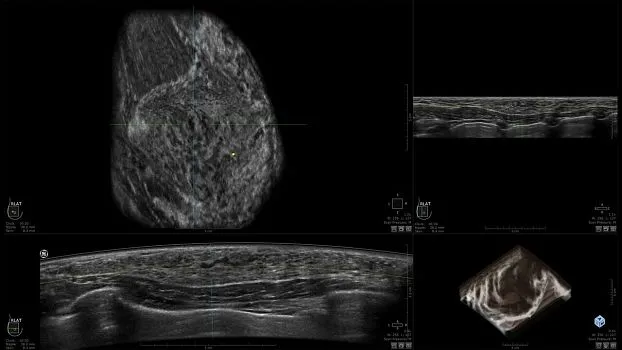

Клинические изображения

• Получение объемных 3D изображений с возможностью покадрового просмотра

• Отображение объемных 3D ультразвуковых изображений, которые состоят из традиционных поперечных и воссозданных коронарных и сагиттальных проекций

• Возможность отображения полного 3D изображения

• "толстый срез" в коронарной плоскости;

• поперечная;

• сагиттальная плоскость;

• радиальный и антирадиальный поворот изображения;

• просмотр только области интереса.

• Изменяемая толщина среза: 0,5 - 10,0 мм (шаг 0,5 мм)